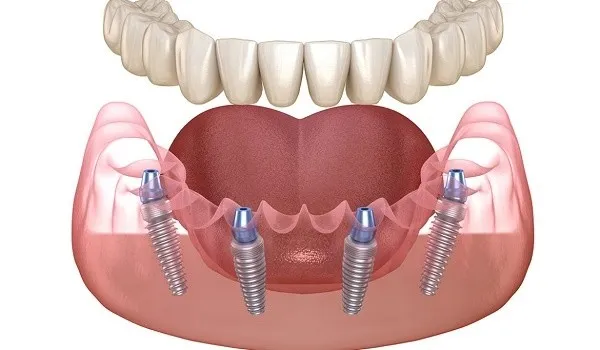

Trong cuộc sống ngày nay, vấn đề mất răng đang trở thành nỗi lo lắng của nhiều người, đặc biệt là người cao tuổi. Việc trồng răng

Trồng răng implant all on 4 là một trong những phương pháp phục hình nha khoa tiên tiến nhất hiện nay, mang lại giải pháp tối ưu